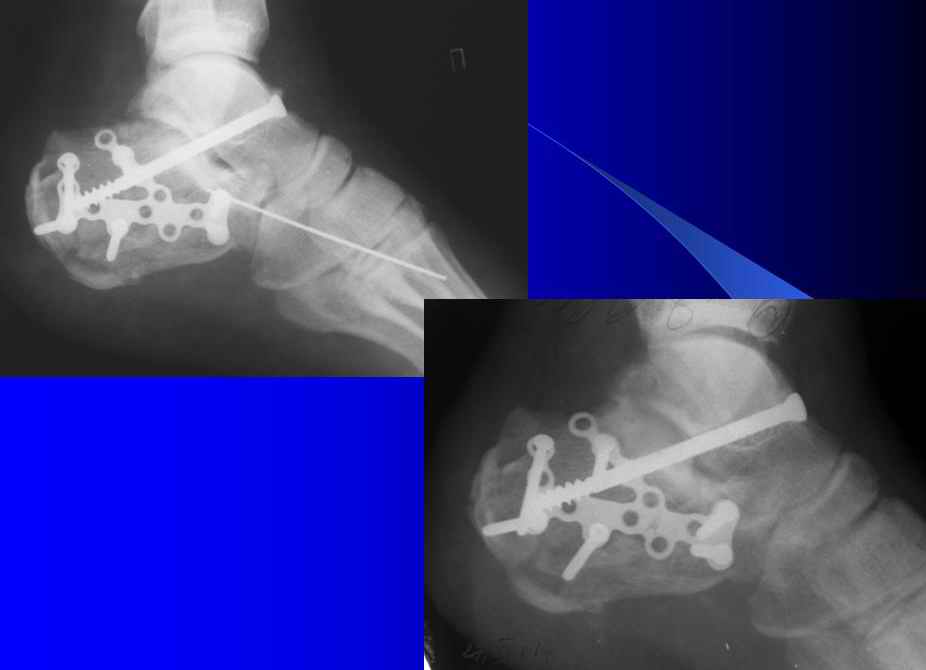

Otkritaya repositsija, fixatija plastinoj. Sprava podtaranniy artrodez.

Справа ситуация сложнее так как имеется помимо перелома имеется вывих тела пяточной костиПоэтому даже если удастся достигнуть хорошей репозиции необходимо сделать первичный подтаранный артродез.Иначе кость не будет держать в своём ложе.Но пластина нужна обязательно чтобы восстановить форму пятки.С уважением Дрягин

Уважаеемый коллега.Слева ситуация достаточно не сложная.Суставной фрагмент вклинился в тело.Необходимо наружным доступом освободить отломки,поднять суставной фрагмент и фиксировать пяточной пластиной LCP.